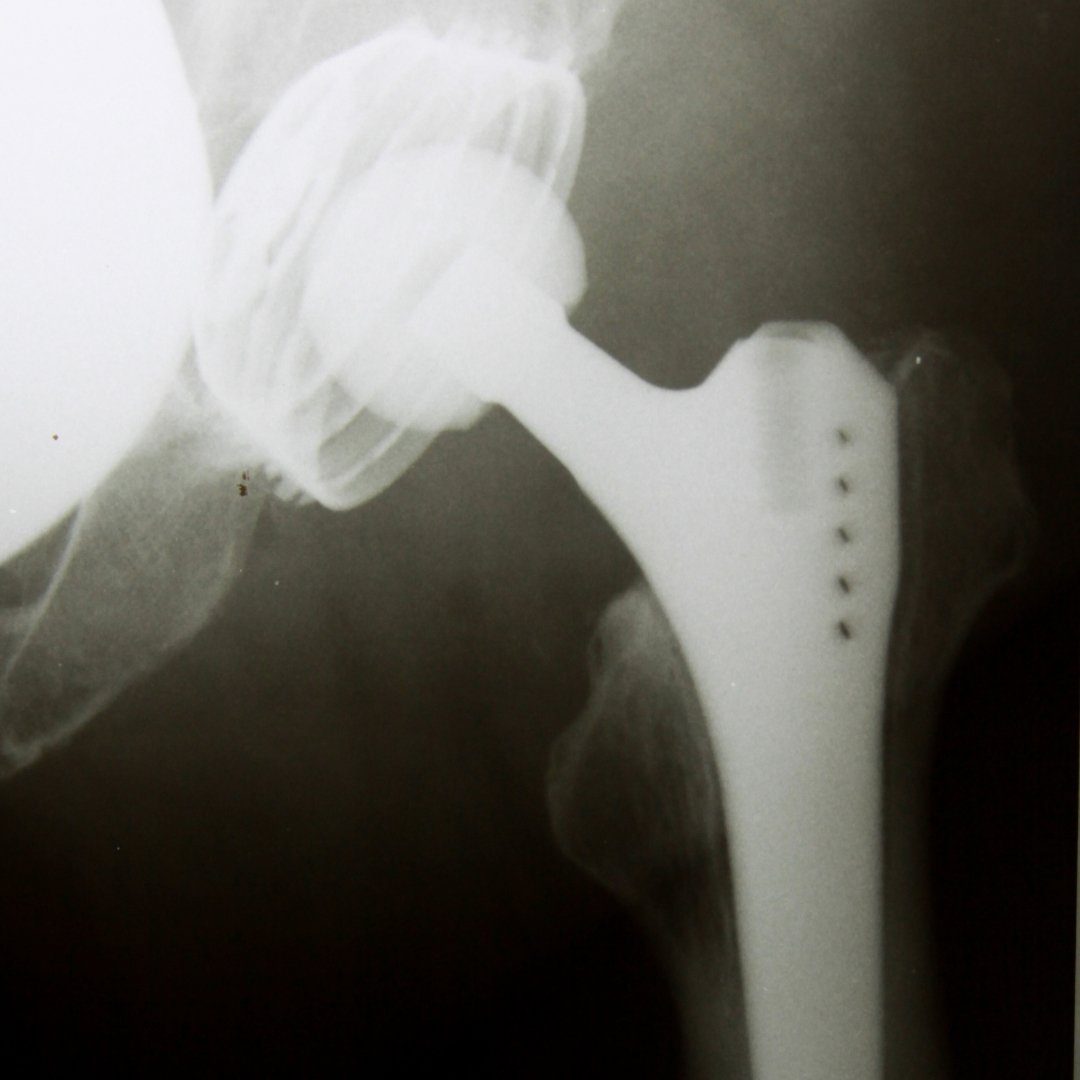

Кульшовий суглоб – один із найважли....